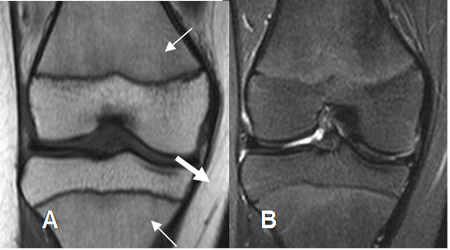

Fig 2 Medula ósea en niño normal

A: RM coronal en T1 y B: RM coronal en STIR. Medula osea amarilla en la epífisis distal del fémur y proximal de la tibia. Medula osea roja en las metafisis con señal intermedia (Flechas delgadas), menor que la grasa. (Flechas gruesas).